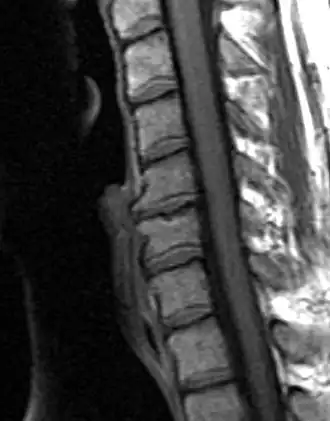

Spinal Arthritis

Degenerative changes observed on the intervertebral joints are not considered osteoarthritis (OA) strictly speaking, since OA only affects synovial joints, whereas intervertebral joints are amphiarthrodial, i.e. cartilaginous joints that allow for mild or minimal movement of the articulating elements.[14] Nonetheless, osteoarthritis and spinal arthritis have a very similar manifestation and they are often grouped together in the bioarchaeological literature. Bioarchaeological and clinical studies have demonstrated that the manifestation of spinal arthritis is linked to factors such as age, sex, body size, mechanical stress, bipedal posture, and others.[15] As with OA, spinal arthritis has been traditionally used in bioarchaeological studies to explore different aspects of social and cultural parameters.

Lesley Gregoricka and Jaime Ullinger from the Ohio State University examined the changes in spinal degenerative disease frequencies of the cervical vertebrae from the Early Bronze Age (3150 – 2300 c. BCE) skeletal assemblage of Bab edh-Dhra’ in Jordan. The aim of the study was to confirm or refute whether an increase in sedentism at the site led to declining workloads. Analysis revealed that the frequency of spinal arthritis decreased from 21% to 13% across the Early Bronze Age at the site. This decrease over time was attributed to a reduction in physical stress on the neck resulting from changes associated with carrying loads on the head. Both authors go on to suggest that the semi-sedentary group of the EB IA (3150 – 3050 c. BCE) were probably practicing small-scale horticulture, yet leaving no significant archaeological remains behind; while the later sedentary group of the Early Bronze Age II-III (2900 – 2300 BCE) at Bab edh-Dhra’ lived year-round next to agricultural fields and streams, therefore, travelling shorter distances for transporting crops and water.[16]

Schmorl’s Nodes

Compressive forces stressing the vertebral column as a result of mechanical loading often cause disc herniation. In turn, this facilitates the formation of cystic lesions referred to as Schmorl’s nodes on the superior and inferior vertebral endplates.[17]